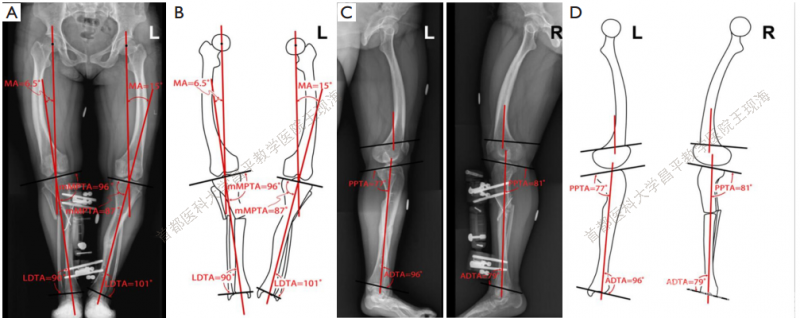

下肢外观有所改善。CORA的平均位置如下:左侧在膝关节方向线上17厘米,右侧在膝关节方向线上12 cm。畸形的评估修正,MPTA改善,左侧由76°-到87°,右边由72°到 96°(Figure 4A,B and Table 2) 。mLDTA,左边从109°到 101°,右边从98°到90°(Figure 4A,B and Table 2) 。

表2 术前和术后参数

L,左;R,右;MA,下肢力线(髋膝踝);mMPTA,胫骨近端内侧机械角;mLDTA,胫骨远端外侧机械角;PPTA,胫骨近端后倾角;ADTA,胫骨远端前倾角。

图4在冠状面和矢状面测量的术后关节方向角。(A)冠状面X线;(B)冠状面下肢轮廓;(C)矢状面X线;(D)矢状面下肢轮廓。

矫正后的双侧力线较术前均明显改善(表 2) 。在最后一次就诊时,PPTA和ADTA接近正常值,得到了明显的矫正(图 4C,D, 表 2) 。在上次访问中,双侧骨质均已愈合(图 5) 。